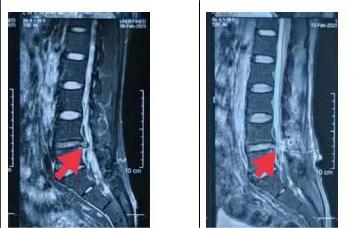

术前术后MRI对比

来就诊的患者大都是长期饱受腰腿痛的折磨,已经严重影响了正常的行走坐立,生活质量严重下降,多方求医尝试了很多治疗方法仍未得到明显好转和根除。我院脊柱外科团队仔细研究每位患者病情,针对每位患者制订个性化治疗方案,选择利用国内较为前沿的新型脊柱微创技术——微创双通道内镜技术(UBE技术)为病人解决难题。脊柱外科团队在完善术前必要检查的前提下,制订了详尽完备的术前规划,分别为患者实施了UBE下椎管扩大减压手术,改术式仅通过2个1cm的小切口便完成了神经减压操作,出血量不到50ml,术后患者腰腿痛症状明显消除,恢复理想,患者及家属对手术疗效非常满意。

胸腰椎椎管狭窄症是指各种原因引起椎管各径线缩短,压迫硬膜囊、脊髓或神经根,从而导致相应神经功能障碍的一类疾病。静卧或休息时常无症状,行走一段距离后出现下肢疼痛、麻木、无力等症状,需蹲下或坐下休息一段时间后,方能继续行走。随着病情加重,行走的距离越来越短,需休息的时间也越来越长。以往腰椎椎管狭窄症的治疗一般都是采用开放减压手术,该术式创伤较大,术后恢复时间也长。而UBE技术仅是在背部建立两个仅约1cm长的小切口(一个视野通道,一个操作通道)便可进行手术操作,在UBE内镜辅助下可完成中央椎管、双侧神经根及侧隐窝狭窄的减压,并可在镜下完成椎间植骨融合。双通道脊柱内镜手术系统弥补了单通道椎间孔镜工作效率低、视野范围小、适应症少的缺点,弥补了大通道技术失血多,创伤面大、视野模糊的不足之处。传统的腰椎开放手术一般术后一周左右才可以下床活动,而UBE手术患者术后一般1-2天就可下床活动,可自行上厕所或起身吃饭,但仍需腰围保护,腰围的保护一般持续到术后1-3个月。